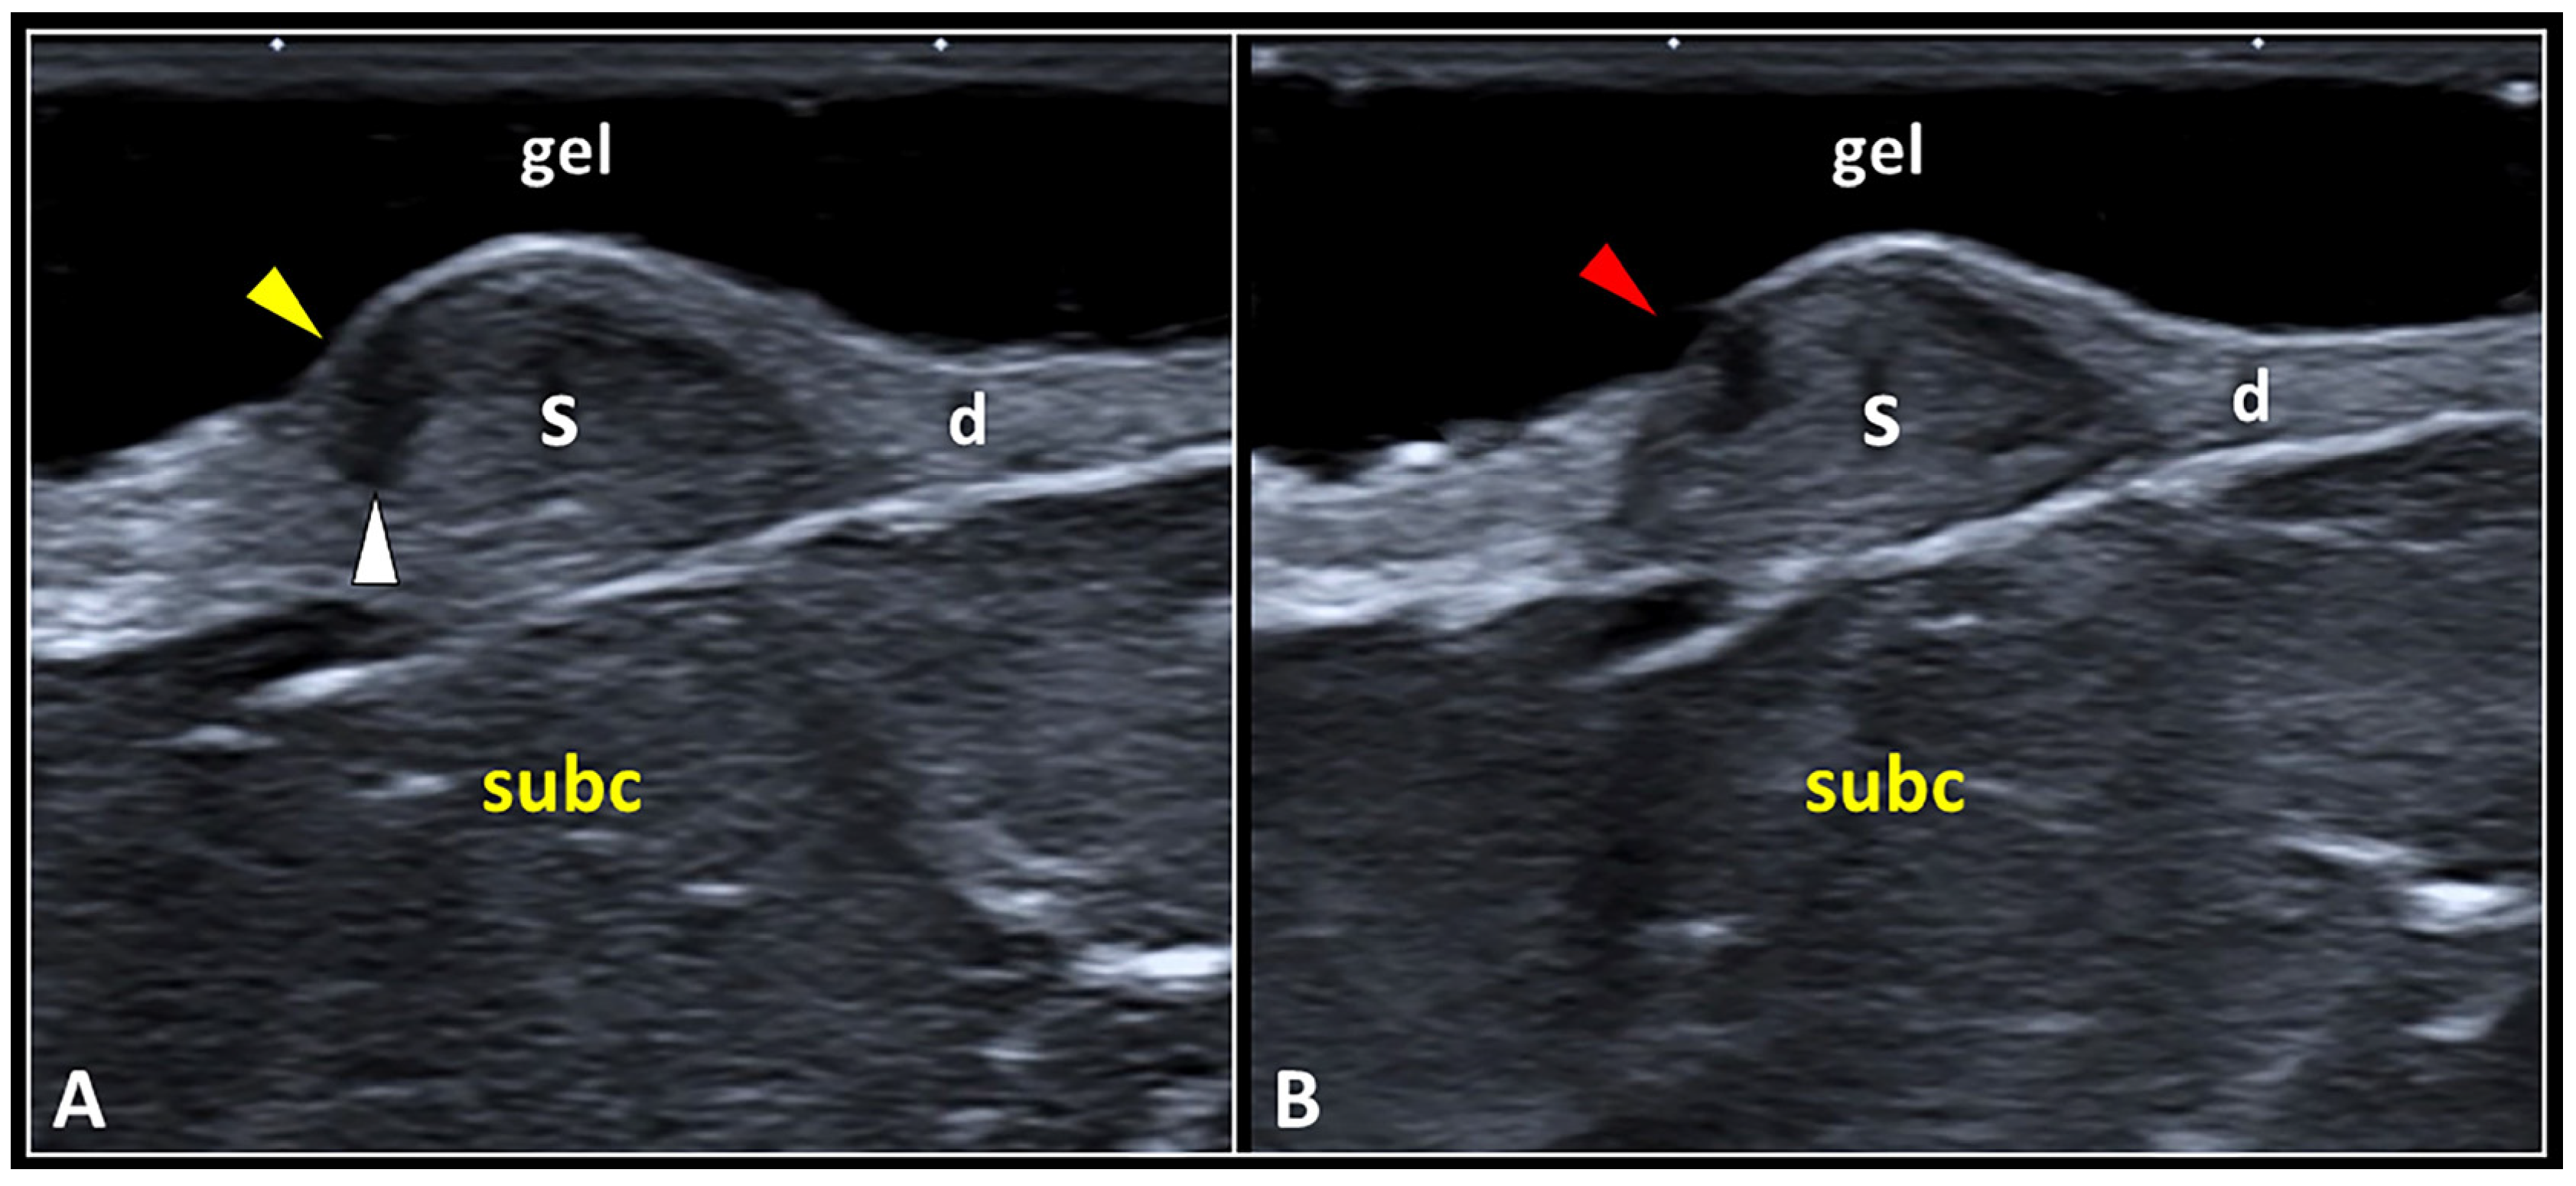

Figure 4.

The dermo-epidermal dissociation. Retraction of the scar tissue (S) may generate a gap (white arrowhead) in between the epidermal (yellow arrowhead) and dermal (d) layers, i.e., dermo-epidermal dissociation (A). This condition can evolve in a focal discontinuity of the epidermis (red arrowhead), probably due to a local hypo-vascularization, with superficial exposure of the underlying scarring tissue (B). subc: subcutaneous tissue.

Focal injury of the epidermal layer overlying the site of dermo-epidermal dissociation is most likely related to local hypoperfusion—with mechanical disruption of the hemidesmosomal adhesion proteins at their attachment to the underlying laminae (lucida and densa). Yet, as previously mentioned, there are terminal arterioles, capillaries, and postcapillary venules arranged in a “candelabra-like loop system” located into each dermal papilla, with ascending arterial and descending venous branches [26,31]. The authors strongly suggest accurately reporting the aforementioned sonographic patterns of the epidermis in patients with skin scars—to plan a suitable treatment to avoid infection of the superficial soft tissues. For instance, special bandages to protect the scarring tissue, and/or topical pharmacological agents to create a protective film over the focal discontinuity of the epidermis can be used. Likewise, in patients with a clinical suspicion of epidermal interruption (after the physical examination), a sterile gel should be adopted to prepare the soft standing pad over the skin scar before the US assessment.